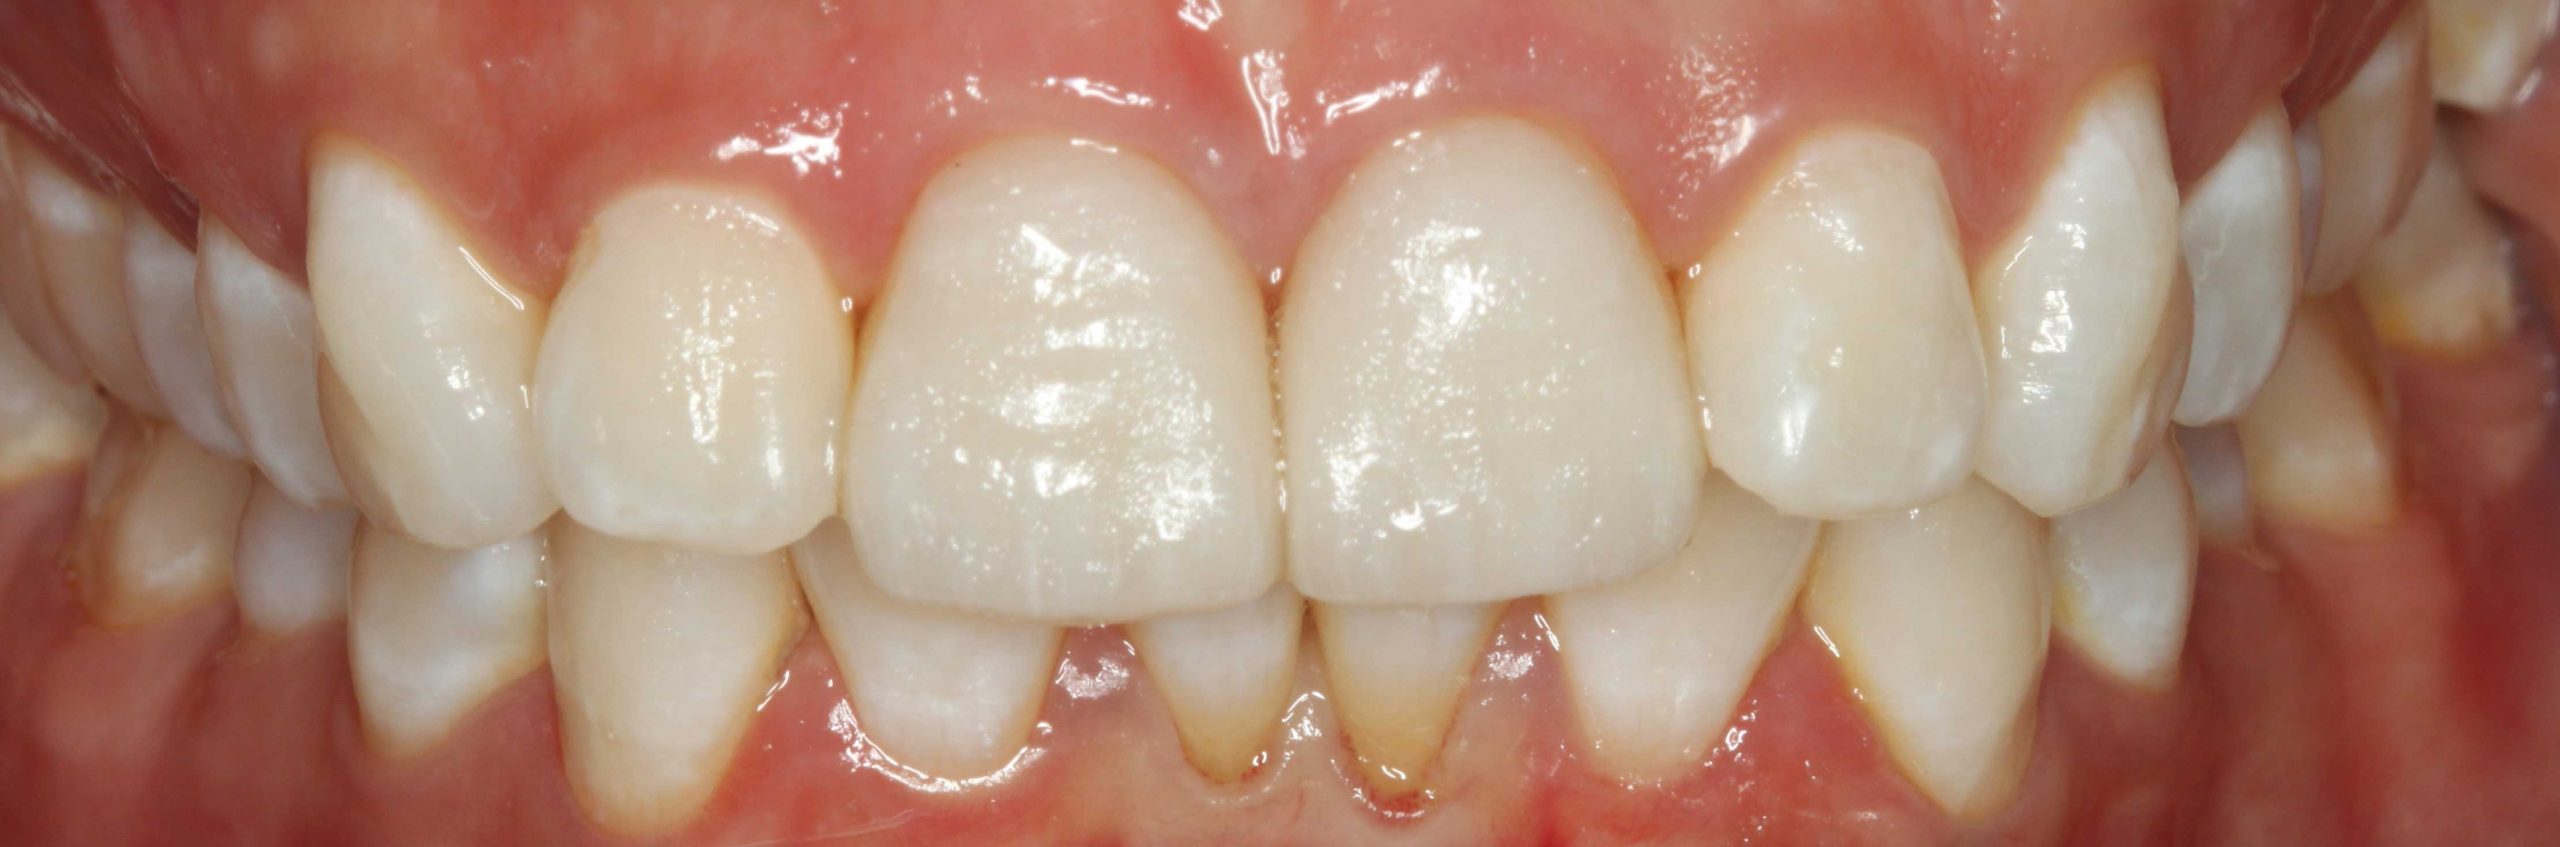

El paciente vino con una sonrisa con coloración más apagada y manchas. Tras el tratamiento con un blanqueamiento dental, se muestra una clara mejoría en luminosidad, con un aspecto homogéneo.